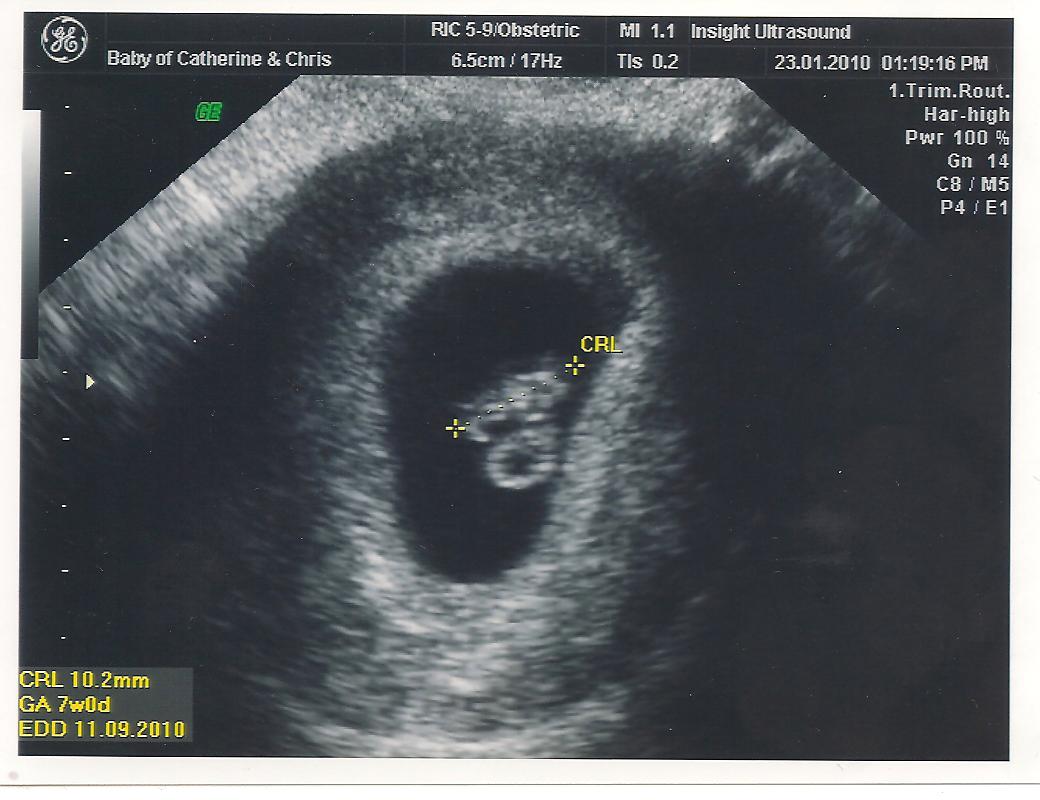

It's a blob, A 7-8 week old blob! It's a chrismoyles.net baby. We know it's pretty early to be announcing but we saw the little heart beat today and we need to tell people because most of our families don't know yet (so please no facebook wall posts about it just yet!)